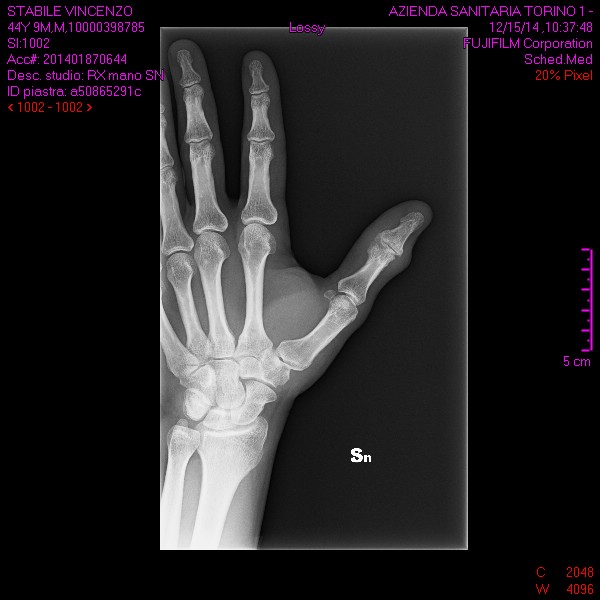

Sono sei mesi che mi sono procurato una frattura parcellare della seconda falange del pollice sinistro e non riesco a muovere come prima il dito a causa di un gonfiore ( edema?) che rende tesissima la pelle rendendo impossibile il piegamento completo.... se sforzo passivamente il dito si piega normalmente come l'altro , segno che il tendine è funzionale , ma attivamente non riesco a cusa dei liquidi presenti sull'articolazione... E' normale tutto cio' dopo sei mesi 6 ???? Grazie per il consulto.

Commento file: queste sono le radiografie fatte giorno 15 dicembre 2014

buonasera, visto lastre. direi che il tempo è eccessivo.

è oppurtuno effettuare una rmn e una visita da un altro medico per avere confronto di pareri e poi valutare.

dopo sei mesi è anomalo che non ci sia un inizio di calcificazione.

una cosa è articolazione, un'altra è la frattura che intende lei.